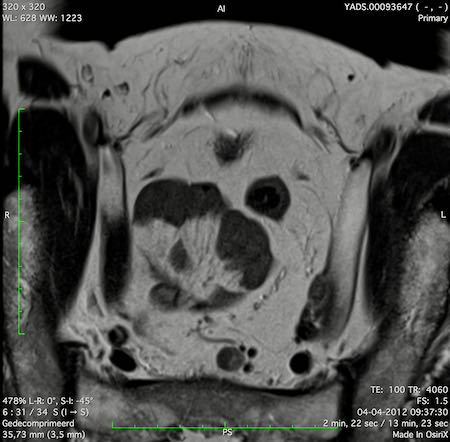

Hình ảnh

Các hình ảnh được cung cấp cho thấy ung thư biểu mô tế bào nhẫn với tình trạng dày lan tỏa thành trực tràng, hình ảnh bia bắn điển hình, và sự xâm lấn mỡ mạc treo trực tràng.